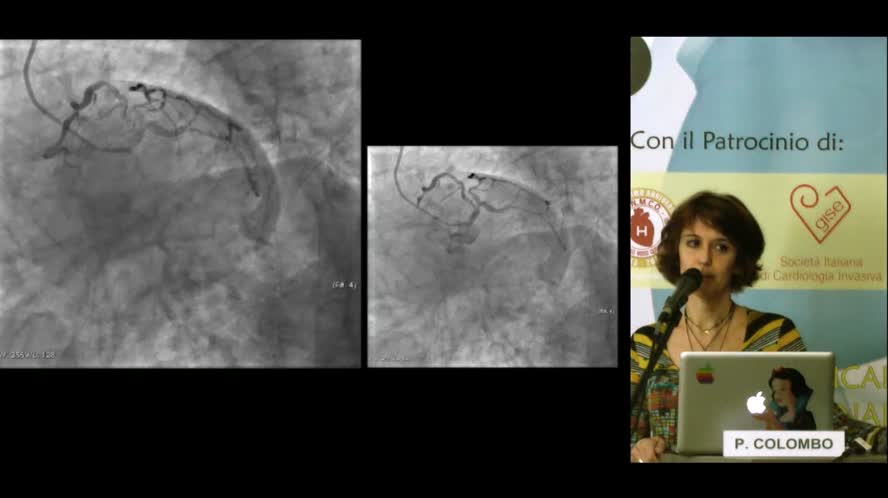

18:05

Cardiochirurgo: meglio conquistarlo e sposare insieme una filosofia

Congresso

: Clinical interventional forum Tosco-Lombardo - SCA e malattia multivaso

Autori

: P. Colombo |

Data

: 04 maggio, 2013 |

Lingua

: ITA |